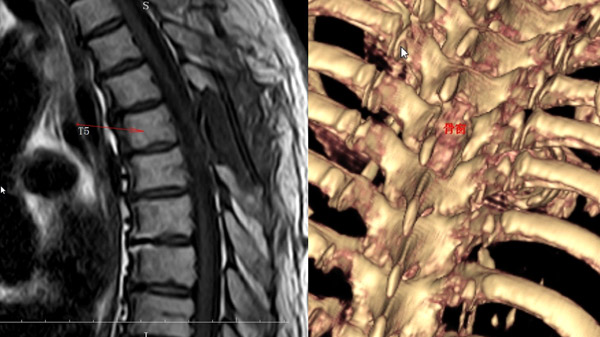

輔助檢查:術(shù)前胸椎MRI可見胸5-6水平椎管內(nèi)占位病變

診斷:胸5-6椎管內(nèi)硬膜下髓外占位病變:脊膜瘤

手術(shù)方案:俯臥位后正中入路胸5右側(cè)半椎板切開顯微鏡下椎管內(nèi)病變切除術(shù)

術(shù)后影像:術(shù)后1天復查MRI可見原胸5-6椎管內(nèi)病變已全部切除